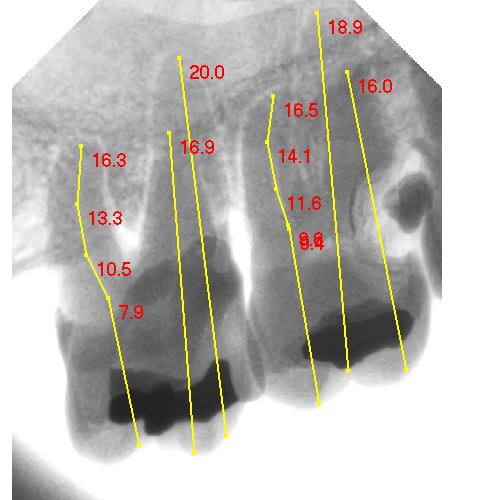

PERIAPICAL PLUS

PERIAPICAL DIGITAL

SERIE PERIAPICAL